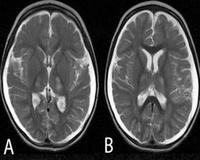

• МРТ головного мозга. На снимках видны зоны умеренного гиперинтенсивного сигнала в затылочных областях коры головного мозга. Для стойких припадков характерно появление участков повышенной интенсивности в области таламуса, продолговатого мозга. В базальных ганглиях, стволе мозга и мозжечке визуализируется прогрессирующая атрофия.